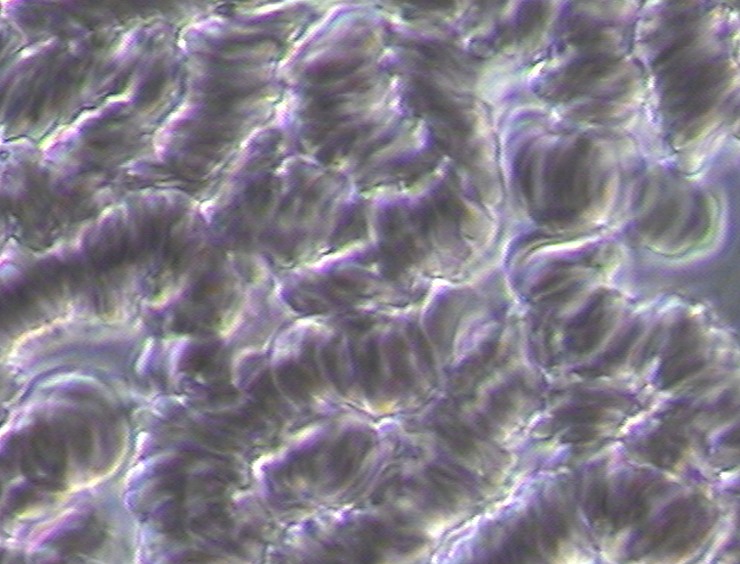

Pathological blood coagulation or disseminated intravascular blood coagulation (DIC) inside the pulmonary vein will prevent the free passage of red blood cells into the alveoli of the lungs via the pulmonary capillaries. {See Phase Contrast Micrograph 3 and 4) Erythrocytes or red blood cells must go into the pulmonary capillaries single file. If they cannot pass into the pulmonary capillaries of the lung to the alveoli this will cause oxygen deprivation that leads to red blood cell hypoxia (carbon dioxide poisoning) degeneration, genetic mutation, sepsis and sudden death.[6][7][8]

Live and Dried Blood smears are both non-invasive blood tests that were used in viewing anatomically the conditions of the red and white blood cells in Disseminated Intravascular Coagulation (DIC), Thrombosis, Rouleau, the ‘Corona Effect’ and Acanthocytosis. (See Phase Contrast Micrograph 7)[12]